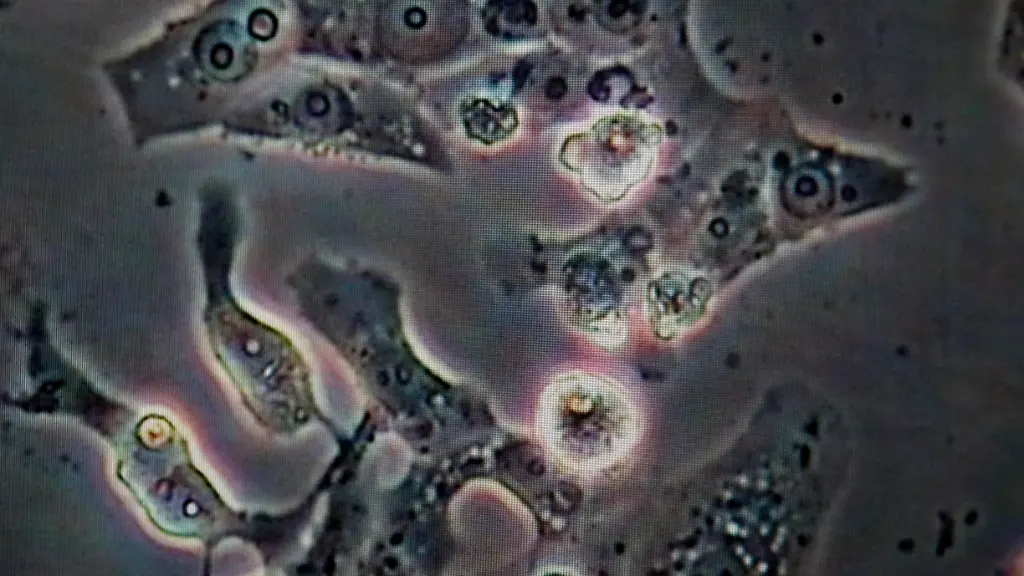

Zellprobe einer Infizierten Amsel: Die Zellen sind vom Usutu-Virus völlig zerstört.

(Foto: dapd)